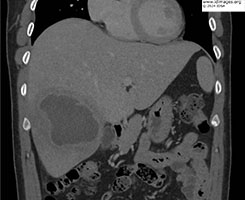

- Initial lab work revealed leukocytosis of 13.6 x103 white blood cells/µL (85% neutrophils, 10% lymphocytes, <1% eosinophils), aspartate transaminase 56 U/L, alanine aminotransferase 60 U/L, alkaline phosphatase 356 U/L and total bilirubin 0.74 mg/dL. Computed Tomography scan of the abdomen with contrast revealed the hepatic abscess (Figure 1).

- Figure 1b: Coronal images of Computed Tomography of the abdomen with contrast demonstrating an 8.2 cm abscess in the right lobe of the liver.